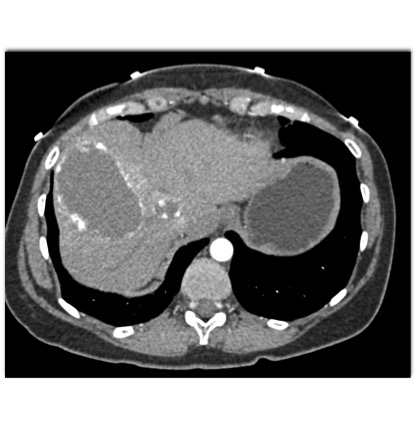

The most likely diagnosis in this case is?

hepatoma

hepatic adenoma

MCN (mucinous cystic neoplasm)

hemangioma